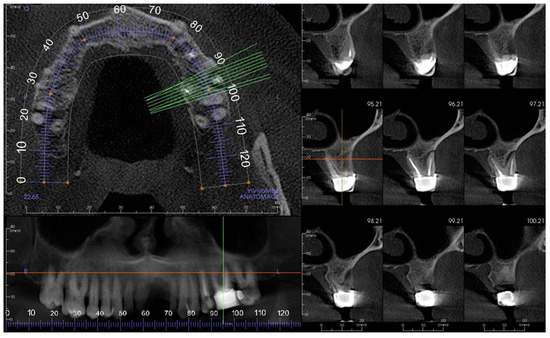

2. Materials and Methods